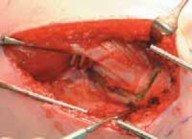

14. The vastus lateralis is divided transversely at its origin on the trochanteric ridge, which corresponds to the inferior level of the insertion of the gluteus medius anteriorly (

TECH FIG 1A

).

15. The vastus lateralis separation is continued inferiorly in an L-shaped manner along its posterior margin just anterior to the insertion of the gluteus maximus (

TECH FIG 1B

TECH FIG 1•

Exposure of the proximal femur through a standard lateral approach.

A.

Origin of vastus medialis at the trochanteric ridge.

B.

Detaching the vastus lateralis from the trochanteric ridge in L-shaped cut.

C.

Subperiosteal elevation of the vastus lateralis from the lateral surface of the proximal femur.

D.

Exposure of the lateral surface of proximal femur, with the

C D vastus lateralis reflected anteriorly.TECHNIQUES